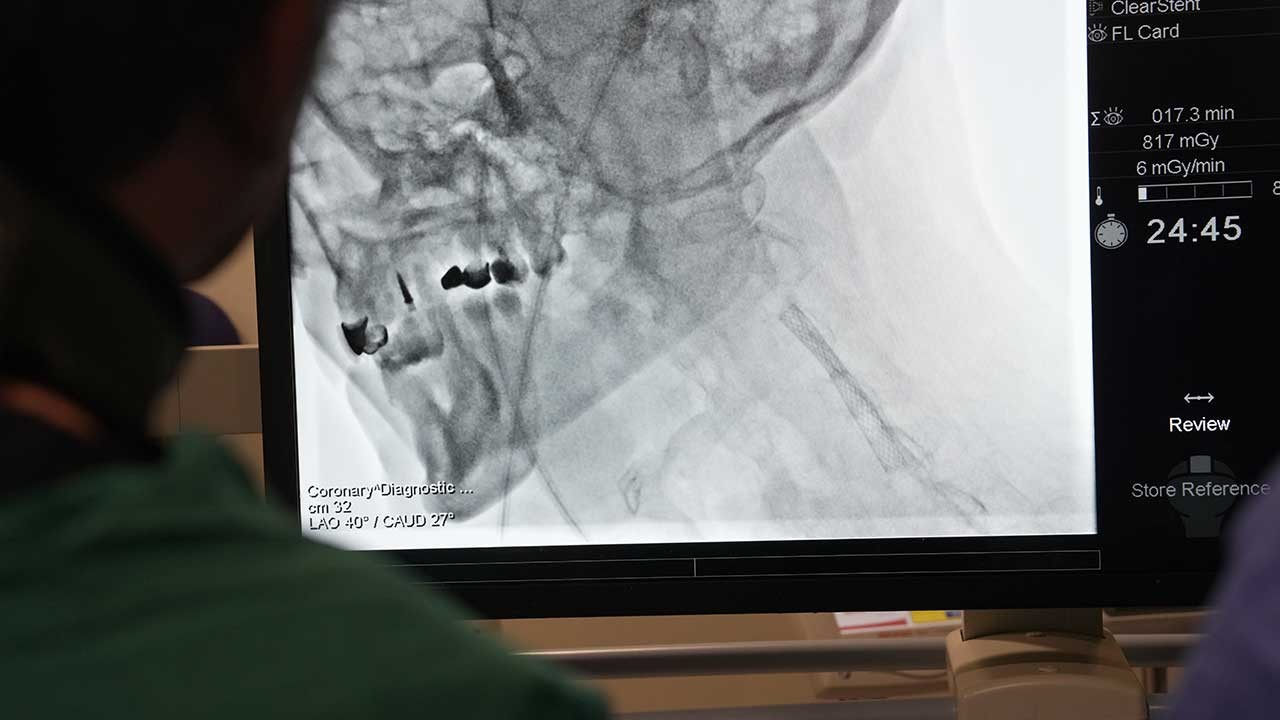

Kardiyoloji uzmanları, yurt dışından gelen doktorlara yönelik ‘İleri Stent Teknikleri’ ve ‘Kronik Damar Açma’ alanlarında eğitim verdi. Prof. Dr. Ertuğrul Okuyan öncülüğünde gerçekleşen eğitim sırasında teorik bilgilerin yanı sıra, canlı operasyonlarla betonlaşmış damarlar açıldı.

Medipol Sağlık Grubu’nun düzenlediği ve bugün başlayan program, Kardiyoloji Uzmanı Prof. Dr. Ertuğrul Okuyan liderliğinde gerçekleştiriliyor. Özellikle Mısır, Pakistan, Tunus ve Cezayir gibi ülkelerden gelen doktorlara modern tıp alanındaki yenilikler ve ileri teknikler aktarıldı. ‘İleri Stent Teknikleri’ ve ‘Kronik Damar Açma’ gibi uygulamalar tüm detaylarıyla paylaşılırken, katılımcılara hem teorik bilgiler hem de canlı operasyon deneyimleri sunuldu. Eğitimler yarın da devam edecek.

Prof. Dr. Okuyan, geleneksel yöntemlerle açılması mümkün olmayan damar tıkanıklıklarının, ileri teknikler sayesinde başarıyla tedavi edilebildiğini de söyleyerek, “Eskiden, çatallanma veya dallanma noktalarındaki darlıklar ya da uzun süredir tıkalı, betonlaşmış, kireçlenmiş damarlar açılamıyordu. Ancak günümüzde kullandığımız ileri teknikler sayesinde bu sorunların üstesinden geliyoruz” diye konuştu.

“Bu tekniklerin temelinde, damar içi ultrason gibi görüntüleme yöntemleriyle damar morfolojisinin detaylı bir şekilde incelenmesi ve özel cihazların yardımıyla tıkanıklıkların açılması yer alıyor” diyen Prof. Dr. Okuyan, “Damar içi tıraşlama yöntemleri, taşırma kateterleri ve özel malzemelerle artık eskiden açamadığımız damarları açabiliyoruz. Bu işlemler, ileri stentleme teknikleri olarak adlandırılıyor” ifadelerini kullandı.